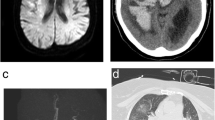

Since the time SARS-CoV-2 appeared in Wuhan, several reports have shown brain and spinal cord infections in some patients. In a retrospective, observational case series reported by Avula A et al., four patients referred to emergency department (ED) with synchronous respiratory and neurologic complaints as altered mental status, unilateral facial drop, slurred speech, aphasia, hemineglect, unilateral weakness and numbness, and hemiplegia. More imaging and laboratory surveys revealed the concurrent ischemic stroke and COVID-19 infection. Patients were not candidate for thrombolysis or neuro-intervention during hospitalization [33]. A case series of 6 ischemic stroke patients was reported by Beyrouti et al. in 2020. Regarding disease severity, 4 cases were severe (with one death) while 2 cases were moderate. Even though therapeutic anticoagulation and multiterritory infarcts were detected in 3 patients, 2 cases had synchronous venous thrombosis and 2 cases developed ischemic stroke. In the laboratory findings, high D-dimer level (all cases), hypoalbuminemia (all cases), high lactate dehydrogenase (all cases), high serum ferritin (5 of 6 cases), high c-reactive protein (CRP) (5 of 6 cases), positive lupus anticoagulant (5 of 6 cases), anemia (5 of 6 cases), high fibrinogen level (4 of 6 cases), high cardiac troponin I (4 of 6 cases) lymphopenia (3 of 6 cases), high prothrombin time (3 of cases), and thrombocytosis (2 of 6 cases) were detected [32]. Hughes et al. reported a 59-year-old man presented with fever and a 4-day history of gradual progressive right-sided fronto-temporal headache. Laboratory surveys showed active COVID-19 infection; moreover, an increase in inflammatory markers and fibrinogen level and decrease in activated partial thromboplastin time (APTT) were observed. Besides CT scan findings, CT venogram filling defects in the right sigmoid and transverse sinus confirmed cerebral venous sinus thrombosis [34]. In a case series of stroke occurring in 19 patients with COVID-19 infection from Italy, seventeen cases (89.5%) were ischemic and 2 others remaining were hemorrhagic (10.5%). Immovilli et al. reported the stroke incidence about 2.2% among hospitalized COVID-19 patients. Stroke etiologies include large artery atherosclerosis, cardio-embolism, small vessel disease, and undetermined factors [40]. Gonzalez-Pinto et al. reported malignant ischemic stroke in a 36-year-old woman. The patient was found with altered level of consciousness, global aphasia, and right hemiplegia. Further investigations demonstrated COVID-19 infection with significant infarct in the territory of the left middle cerebral artery (MCA) with mild midline deviation. Patient’s clinical status was not suitable for any other procedures, and finally, she passed away [35]. In a case series by Al saiegh et al., 2 patients pretended with neurological symptoms as sudden onset headache, mental status change, hemiparesis, and aphasia with real-time PCR positive results for SARS-CoV-2. Despite positive real-time PCR of nasal sample, SARS-CoV-2 real-time PCR for cerebrospinal fluid (CSF) was negative for 2 consecutive times [36]. In a recent case report, Viguier et al. presented a 73-year-old man who developed an acute ischemic stroke after a week history of fever and dry cough. On admission, the patient had right-sided hemiparesis with aphasia. Head and cervical CT angiography revealed a large floating thrombus appended to a non-stenosing plaque on the left common carotid artery wall. Head CT scan and magnetic resonance imaging (MRI) confirmed acute ischemic stroke in the left common carotid artery territory. Patient was undergone anticoagulation with low molecular heparin (enoxaparin b.i.d). After 15 days on follow-up with ultrasound examination, there were no recurrent emboli and previous thrombus but a moderate aphasia persisted [37]. Oxley et al. reported consecutive 5 patients aging younger than 50 years old with ischemic stroke diagnosis referring in a 2-week period from March 23 to April 7, 2020. Surprisingly, all mentioned patients developed large vessel involvement with various clinical presentations as altered level of consciousness, headache, horizontal gaze, homonymous hemianopia, ataxia, unilateral hemiplegia, dysphasia, dysarthria, and sensory deficit. All patients’ nasal swab PCR were positive for SARS-CoV-2, while just 2 out of 5 cases developed respiratory symptoms. Mild-to-moderate systemic coagulopathies were detected in laboratory findings of 4 patients [38]. An observational study on 184 critically ill intensive care unit (ICU) admitted patients with proven SARS-CoV-2 pneumonia showed an incidence of 31% thrombotic complications. Despite standard thromboprophylaxis measures, 81% developed pulmonary embolism (PE), 21% diagnosed with venous thrombotic events (VTE), and arterial thrombotic events in 3.7% of patients. Age and coagulopathy were independent predictors of thrombotic events [41]. Yeboah and colleagues published a case report of a 49-year-old woman with the complaint of fever, fatigue, and progressive shortness of breath. Laboratory findings showed CRP, lactate dehydrogenase, procalcitonin, and ferritin elevation. At the second day of admission, she developed sudden left-sided hemiparesis, sensory neglect, left hemianopsia, and right gaze deviation with the National Institutes of Health Stroke Scale (NIHSS) 14. The CT angiography and CT perfusion showed thrombus in the right carotid artery and filling defect in left carotid artery bulb. Patient was gone under treatment with alteplase, mechanical thrombectomy, and retrievable stent appliance in the right cerebral artery. NIHSS alleviated to 0 at discharge and due to thrombus in the left cerebral artery, a 6-month course of apixaban is recommended [39]. Belani et al. in a retrospective case-control study on 41 cases with imaging evidence of acute infarction and 82 controls of 6 New York City hospitals displayed 43% of case concurrent COVID-19 infection while 18.3% of control COVID-19 infection. COVID-19 had a significant independent association with acute ischemic stroke (OR = 3.9, 95% CI, 1.7–8.9; P = 0.001) [42]. They recommended more aggressive monitoring for stroke in COVID-19 patients [42]. A single-center, prospective observational study 6 weeks after COVID-19 pandemic declared a mean fall of 38% in new stroke diagnosis with similarity in monthly new large vessel occlusions (LOVs) strokes, while the proportion of new LVOs doubled approximately [43]. Table 1 summarizes the recent evidence about SARS-CoV-2 and stroke incidence.